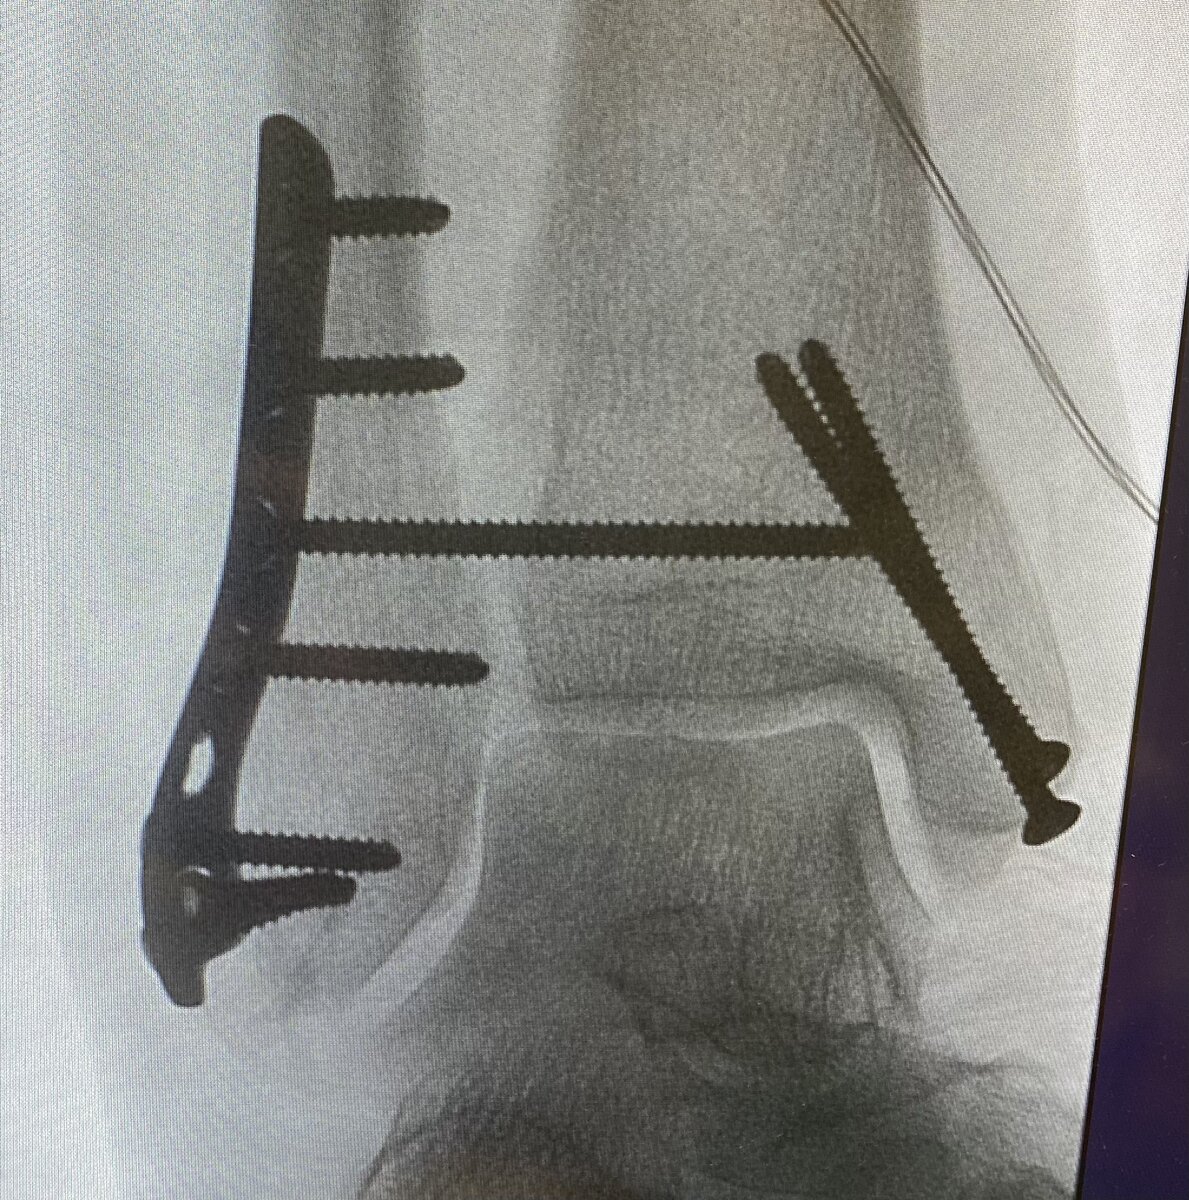

При переломе обеих лодыжек зачастую рвется дистальное синдесмозное соединение между малоберцевой и большеберцовый костями. Для фиксации и сращения синдесмозного соединения на операции хирург устанавливает в пластину длинный кортикальный винт. Данный винт через 8 недель после операции необходимо удалить в стационаре.

Длинный кортикальный синдесмозный винт, проходящий через пластину

При достижении срока 8 недель и снятии позиционного винта можно давать нагрузку до полной на оперированную конечность и откладывать это не стоит, чтобы не развились контрактуры в голеностопном суставе.